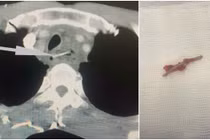

Tưởng do Covid-19 và bệnh phổi tắc nghẽn mạn tính vì ho người đàn ông không ngờ xương trú ngụ trong phổi 3 tháng gây mô hạt, bám giả mạc do thói quen thích ngặm xương chấm mắn ớt.

(khoahocdoisong.vn) - Hóc xương rất nguy hiểm, tùy vào vị trí có thể gây đâm xuyên vào phổi, nguy cơ chảy máu đường thở, nhiễm trùng, áp xe phổi thậm chí tử vong cao nếu không được xử trí sớm.

(khoahocdoisong.vn) - Trong bữa ăn, nhất là bữa ăn có cá thì không nên nói chuyện nhiều mà nên tập trung ăn để không hóc. Hóc xương cá rất nguy hiểm. Đã có những trường hợp hóc xương, xương chui vào phế quản gây ho, sốt liên tiếp, đau ngực, sau bệnh nhân ho ra cả máu.